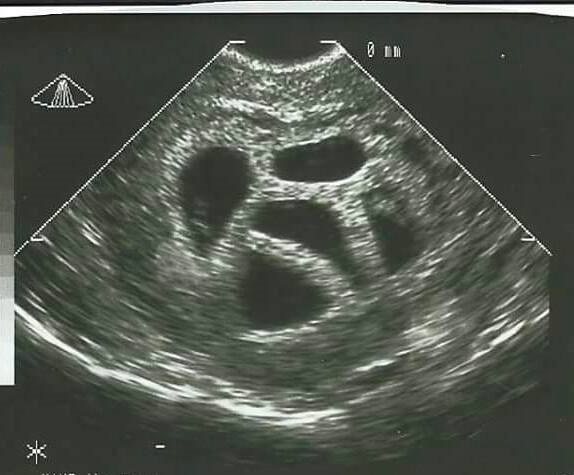

Danas su njezine petorke odrasli ljudi, a 20 godina kasnije, Susan je objavila fotografiju svoje djece uz fotografiju s njihovog ultrazvuka.